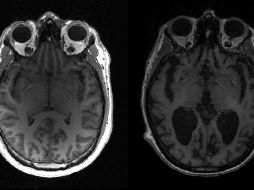

Tecnología Científicos descubren causas del avance del mal de Alzheimer en el cerebro 29 de octubre de 2021 - 14:35 hs Alzheimer Enfermedades